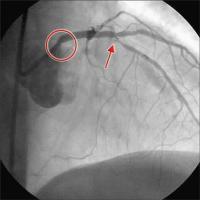

Filmsequenz zu Abbildung 1: Linke Koronararterie RAO/Kranialprojektion 50 % Ostiumstenose Hauptstamm, Bifurkationsstenose LAD – 1. diagonaler Ast (echte Bifurkationsstenose Typ IV ICPS- Klassifikation ), Y-konfigurierter Abgang des Seitenastes. Kollateralen zur verschlossenen RKA. |